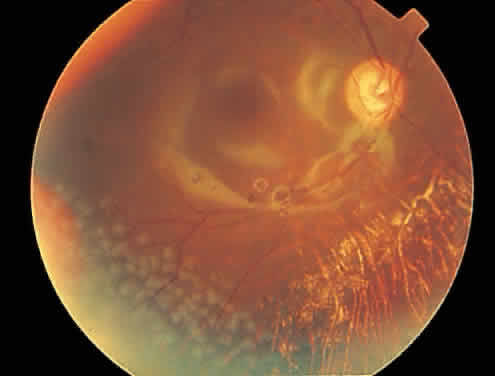

Rhegmatogenous retinal detachment occurs in 10% to 20% of eyes with CMV retinitis.37–39 However, before the AIDS epidemic, there were only five reported cases of this association.10,40 In patients living more than 1 year with CMV retinitis, risk of retinal detachment may be as high as 50%,41 which increases if more than 25% of peripheral retina is involved by disease.41,42 Retinal breaks in eyes with CMV retinitis typically occur within or at the border of necrotic atrophic retina (Fig. 6).43 The ensuing retinal detachments are typically difficult to repair with standard scleral buckling procedures. This is because of the location and number of retinal breaks, the difficulty in visualizing all breaks in necrotic retina, and the high incidence of associated proliferative vitreoretinopathy. In many cases, pars plana vitrectomy and retinal tamponade with silicone oil or long-acting intraocular gas is indicated (Figs. 7 and 8).37,44,45 However, scleral buckling may be considered in small peripheral retinal detachments when the entire involved area can be completely placed on the element. Laser photocoagulation demarcation has also been described to delimit macula-sparing CMV-related retinal detachment.46 Although anatomic success of macular reattachment with surgery is high, the visual results are often limited by the underlying disease process.47 When considering surgical repair of CMV-induced retinal detachment, consideration should be given to the potential for ambulatory vision, the patient's systemic condition and the status of the fellow eye.

Fig. 6. A shallow cytomegalovirus-related retinal detachment is present inferiorly and involves the fovea.

Fig. 7. Repair of the eye in color plate H with silicone oil. Note the silicone oil reflections in the macula.

Fig. 8. Repair of a cytomegalovirus-related rhegmatogenous retinal detachment with pars plana vitrectomy and silicone oil tamponade. Reflections from silicone oil are noted in the macular region. Postoperatively, laser photocoagulation was required inferotemporally to wall off a small area of peripheral subretinal fluid.